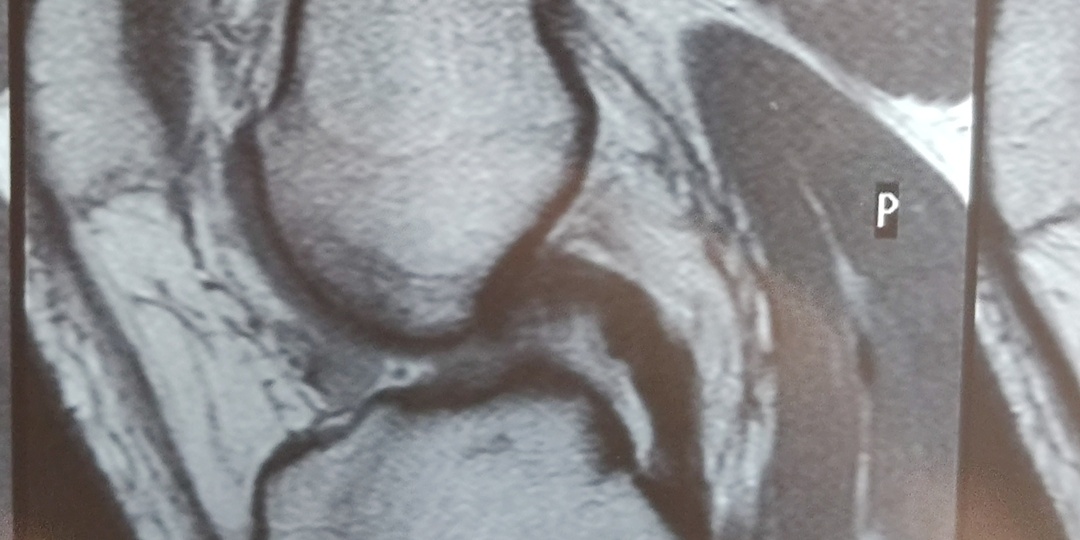

Операция по пластике передней крестообразной связки

Итак, 24 декабря 2025 года на своей тренировке я получила травму. Тотальный разрыв передней крестообразной связки правого колена. А здесь история о непосредственно операции ПКС, проведенной врачом Галимовым Шамилем Камилевичем в Жуковской областной больнице. Операция была проведена по ОМС. О госпитализации : Выехали с Димой в 6:10 примерно из Серпухова, здесь, в Жуковском, были в 8:30. В машине позавтракала супом и бутербродами 😂 А потом пошли сдаваться. Проверили мои анализы, заполнили бумаги. Сдали на хранение куртку, ботинки и чемодан (предварительно его выгрузив в палате). Дима проводил меня до палаты и поехал домой. Палата моя после входа имеет два разветвления через общий предбанник: для мужчин и для женщин. Далее женская комната четырёхместная, здесь две женщины, обе с заменой тазобедренного сустава. Обе выписываются сегодня, одна уже попрощалась и уехала. Так что я скоро окажусь здесь одна. Сегодня у меня взяли кровь на группу. Хоть у меня и есть такой анализ, им нужен

Согнутое разогнуть!

История о 12 января 2026 года

Рассказала сегодня врачу про мои неприятные ощущения при полном разгибании колена. В надежде, что он скажет, что это пройдет после пластики. Врач сказал, разгибайте, что не разгибается, сейчас, а то после операции неприятных ощущений добавится 😁

Понял, принял, разогнул. Вообще, прогресс по реабилитации колена идёт очень интересно. Колено стало как и раньше нормально